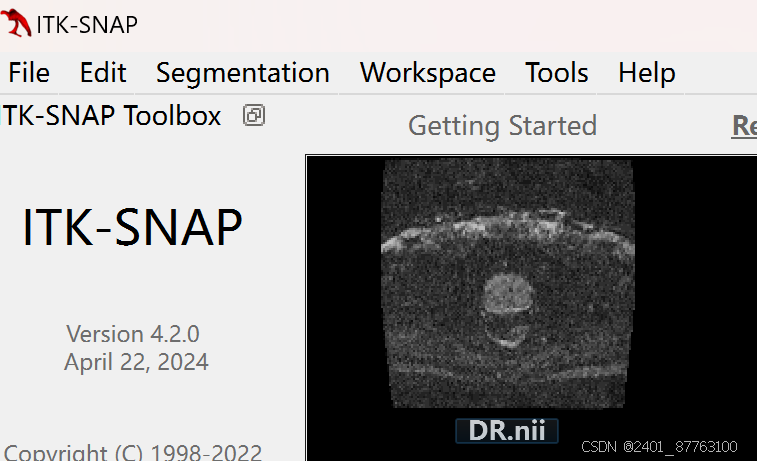

第二步打开itk,勾画ROI----注意:你也可以不勾画ROI计算图像整体的SNR

我的操作步骤是勾画ROI计算ROI内的SNR

把你刚刚转换的NII格式文件拖进去

在此只介绍一种勾画ROI的方法,点击小笔勾画每一层图像你想要的ROI,左键勾右键橡皮擦

勾好后点击segmentation--save segmentation image

自己保存路径。